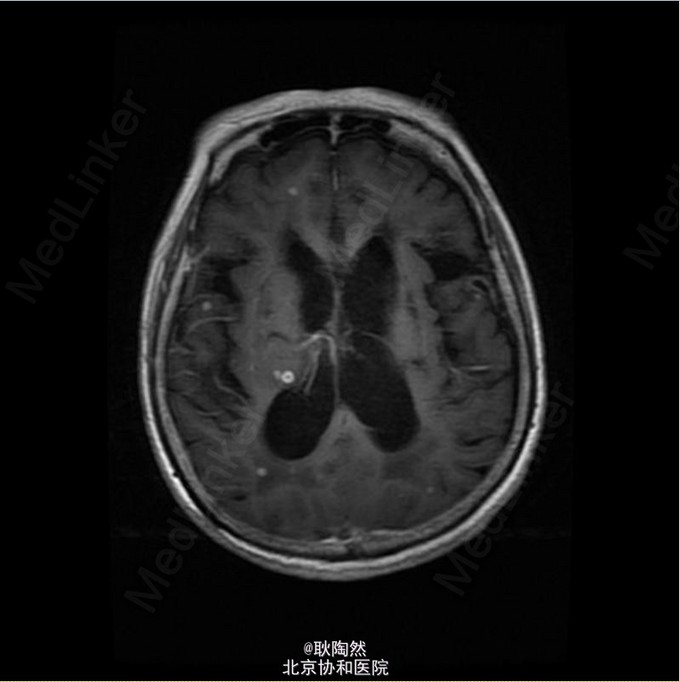

患者75岁老年女性,因“间断发热1年余,乏力、少语2周”于2014-12-25入院治疗。 2013年起患者无明显诱因出现发热,每日午后温度渐高,Tmax39℃,次日凌晨可降至正常。伴乏力,无盗汗、畏寒寒战、咳嗽咳痰等表现。外院胸部CT提示“肺部感染”,予莫西沙星治疗后体温正常。 2013-3患者出现T12椎体骨折,行手术治疗,术前有发热表现,予莫西沙星抗感染治疗后体温正常。2014-5因再次出现腰痛复诊,因前次手术窦道(左髂)迟迟未愈合,于左髂处取活检:坏死性肉芽肿,伴死骨形成,可见多核巨细胞及类上皮细胞,抗酸染色(-),不除外结核。 后患者间断发热。2014-8胸部CT示:右上肺尖后段、右中叶外侧段、左下肺外侧段散在片絮、云雾状不规则高密度灶,密度不均,提示感染;纵膈内未见肿大淋巴结。右肺病灶行肺穿活检:可见肺组织及部分横纹肌组织,肺组织变性坏死,周围小灶肉芽肿形成,纤维组织增生,慢性炎症细胞浸润,部分细胞增生。抗酸(-),PAS(-),六胺银(-)。 2014-12起患者出现神情淡漠,懒言少语,乏力加重,不能坐起或下床。遂入我科。 入我科后查PPD皮试:(+++);血T-SPOT.TB:MLC+IFN(A) 36SFC10^6MC,MLC+IFN(B) 704SFC10^6MC; 胸腹盆CT(平扫):右肺上叶后段胸膜下肿块大致同前;两上肺及右中肺粟粒样结节并两肺多发斑片索条及散在钙化灶,考虑结核性病变;两肺门多发钙化灶,纵隔多发淋巴结;双侧胸膜增厚,大致同前;胸8-腰4 椎体多发内固定器,部分椎体骨质破坏,可为椎体结核术后改变;胸11-腰3 椎体左旁多发低密度影并环形强化,考虑椎旁脓肿;骶骨前方、直肠后方片状低密度影,渗出性改变不除外。 行腰穿:脑脊液压力为88mmH2O。脑脊液常规:外观 无色透明,细胞总数 12*10^6/L,白细胞总数 0*10^6/L,单核 0,多核 0;脑脊液生化:CSF-Pro 0.76g/L,CSF-Cl 115mmol/L,CSF-Glu 1.5mmol/L。脑脊液抗酸染色(-)、脑脊液结核、非结核分枝杆菌DNA(-);脑脊液T-SPOT.TB:MLC+IFN(A) 24 SFC10^6MC,MLC+IFN(B) 132 SFC10^6MC;脑脊液细胞学:结论:淋巴细胞性炎症,WBC 1000/0.5ml,AL 阳性(+),AM 阴性(-),PC 阴性(-),TC 阴性(-),RBC -,CL ++,LY% 90%,MONO% 5%,NEUT% 5.000%; 考虑患者为播散性结核感染,有肺、骨、中枢神经系统受累。予异烟肼、利福喷丁、乙胺丁醇、拜复乐四联抗结核治疗。